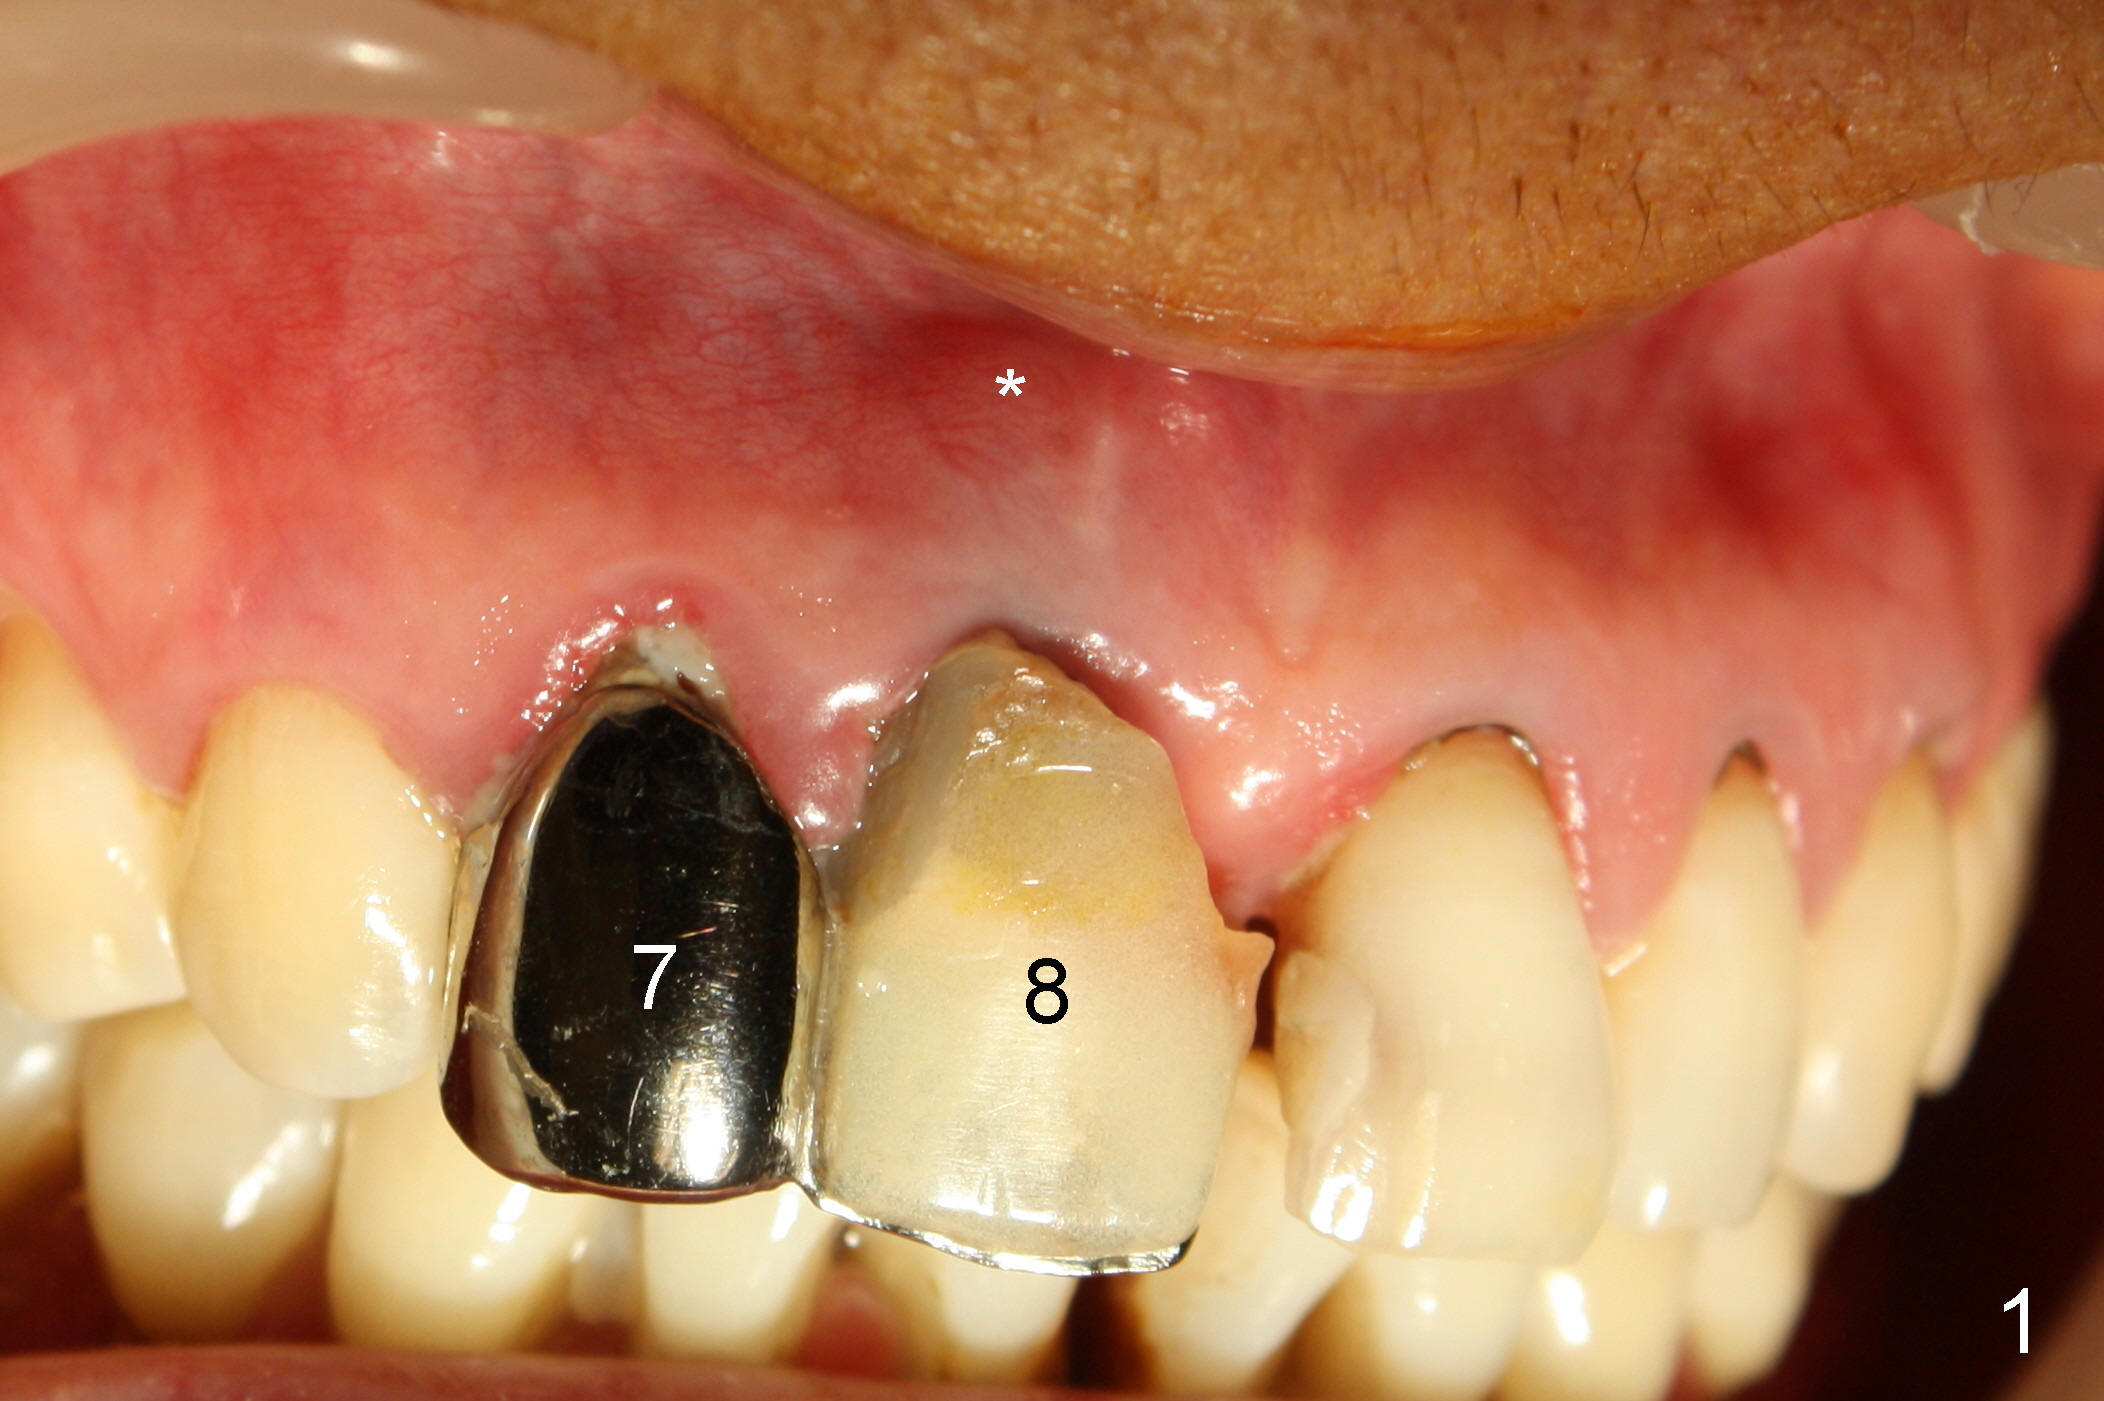

A 64-year-old lady requests replacing #7 and 8 crowns (Fig.1,2). When #8 is extracted, the labial plate is found to be missing (Fig.3). Following 2 mm pilot drill (Fig.4,5 P), 3.8 mm tap drill (Fig.6,7 T) and 4.5x14 mm implant (Fig.8 I) and 4.8 mm abutment (Fig.9 A), corticocancellous bone is harvested from the left tuberosity and placed in the labial gap of the socket (Fig.10 G). Collagen dressing is placed over the bone graft (Fig.11 C). The former is secured in place by an immediate provisional (P).

The patient returns for follow up 8 days postop and the labial margin of the provisional looks long. The metal crown is changed to a provisional at the visit. Eight days later, the provisional at the site of #8 is removed for labial margin trimming; the labial gingiva heals (Fig.14 *). The labial plate remains slightly convex (Fig.15). The labial margin of the provisional at the site of #8 is at the same level of that of #9.

Four-month follow up shows that bone graft from the tuberosity appears to have healed with the implant microthreads (Fig.17 *); there is a diastema between #8 and 9 (arrowheads). Before removal of the provisionals of #7 and 8 for final impression, new composite is added to the mesial surface of #9 as the first step of closure of the diastema (Fig.18 <).

One year post cementation, there is cortical bone formation mesial to the implant (Fig.19 <). Buccal concavity is minimal (Fig.20).